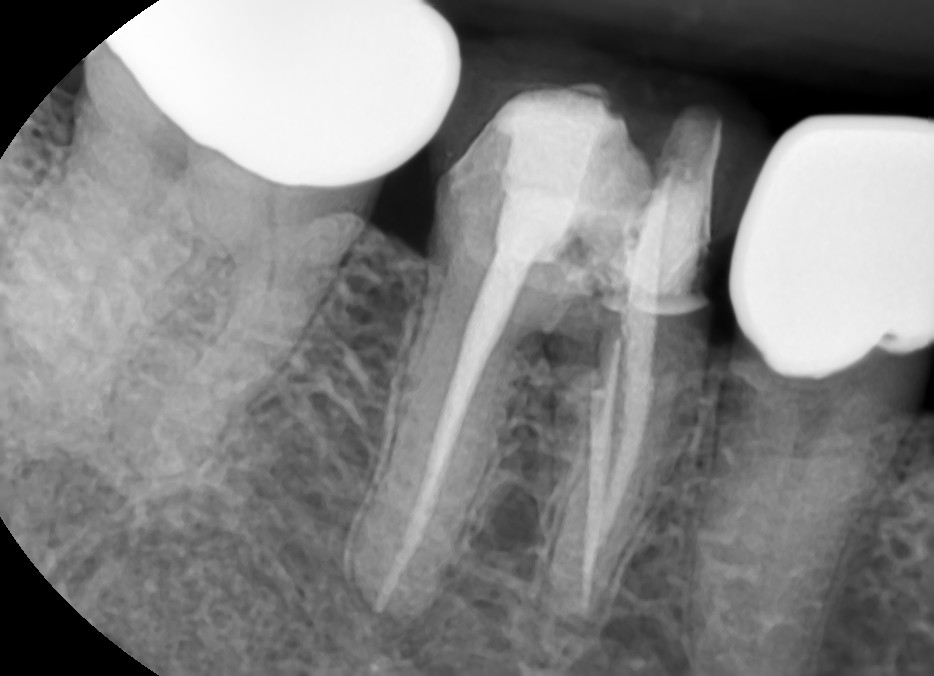

해당 치아의 보철물을 제거하고 신경치료 를 다시 한 방사선 사진입니다.

첫번째 방사선 사진에서 볼 수 없었던 하나의 신경관이 찾아져서 치료가 되어있는 것을 볼 수 있습니다.

신경치료 다시 한 후 환자분의 씹을 때마다 아프다는 증상은 많이 개선되었습니다.